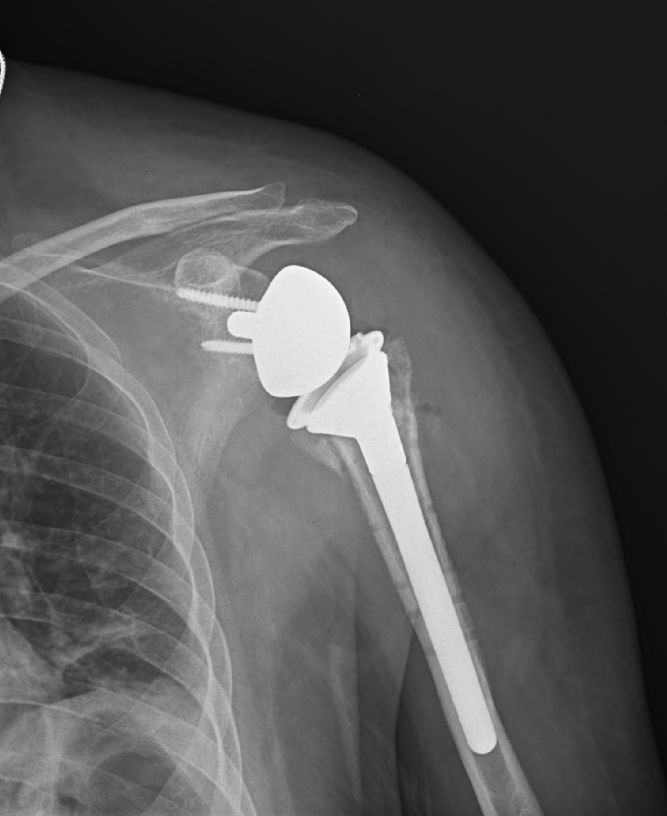

術(shù) 前

咦??jī)蓚€(gè)假體安裝位置是不是反了?稍微對(duì)人體構(gòu)造有了解的人都不難看出這一點(diǎn)。

對(duì),裝反了!故意的!該手術(shù)之所以稱為“反式肩關(guān)節(jié)置換”,就是這個(gè)原因。

徐主任介紹,這是目前國(guó)際上最先進(jìn)的手術(shù)方案,嘉興罕見(jiàn)。過(guò)去,針對(duì)巨大肩袖損傷患者,一般按照人體正常構(gòu)造進(jìn)行順置型肩關(guān)節(jié)置換術(shù),但大量病例顯示,順置型肩關(guān)節(jié)置換術(shù)術(shù)后不盡理想,患者常發(fā)生肩關(guān)節(jié)脫位、活動(dòng)障礙等情況。

經(jīng)過(guò)國(guó)內(nèi)外骨科專(zhuān)家“大?!钡呐?,研究出“反式肩關(guān)節(jié)置換”術(shù),帶來(lái)的好處顯而易見(jiàn),術(shù)后肩關(guān)節(jié)更加穩(wěn)固,大大減輕了病人的痛苦。